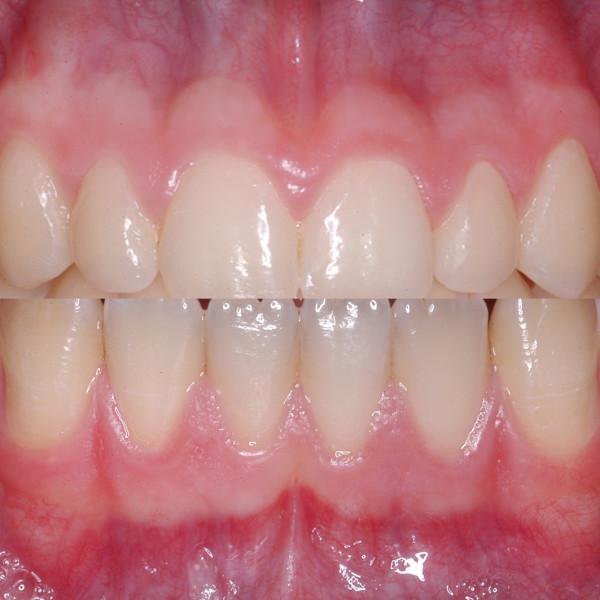

Besides the color of the teeth the color of the alveolar gingiva plays a crucial role in esthetic rehabilitation in dento-alveolar treatment. Whereas nowadays the color of the teeth can be determined exactly and individually, the specific influence of the red color of the gingiva on treatment has not been assessed yet. The aim of this study was to evaluate the vascularization as the basis for gingival esthetics.

Standardized photographs of defined areas of the alveolar gingiva in operated and non-operated patients were taken and assigned to groups with same characteristics after color comparisons. In addition, histologic and immunohistologic analyses of gingival specimens were performed for qualitative and quantitative assessment of vessels and vascularization. Finally, colors and number of vessels were correlated.

Our results demonstrated three different constellations of colors of the alveolar gingiva in healthy patients. The operated patients could not be grouped because of disparate depiction. There was a clear correlation between color and vessel number in the alveolar gingiva.

Our investigations revealed the connections between vascularization and gingival color. Recommendations for specific change or even selection of colors based on the results cannot be given, but the importance of vascularly based incision lines was demonstrated.